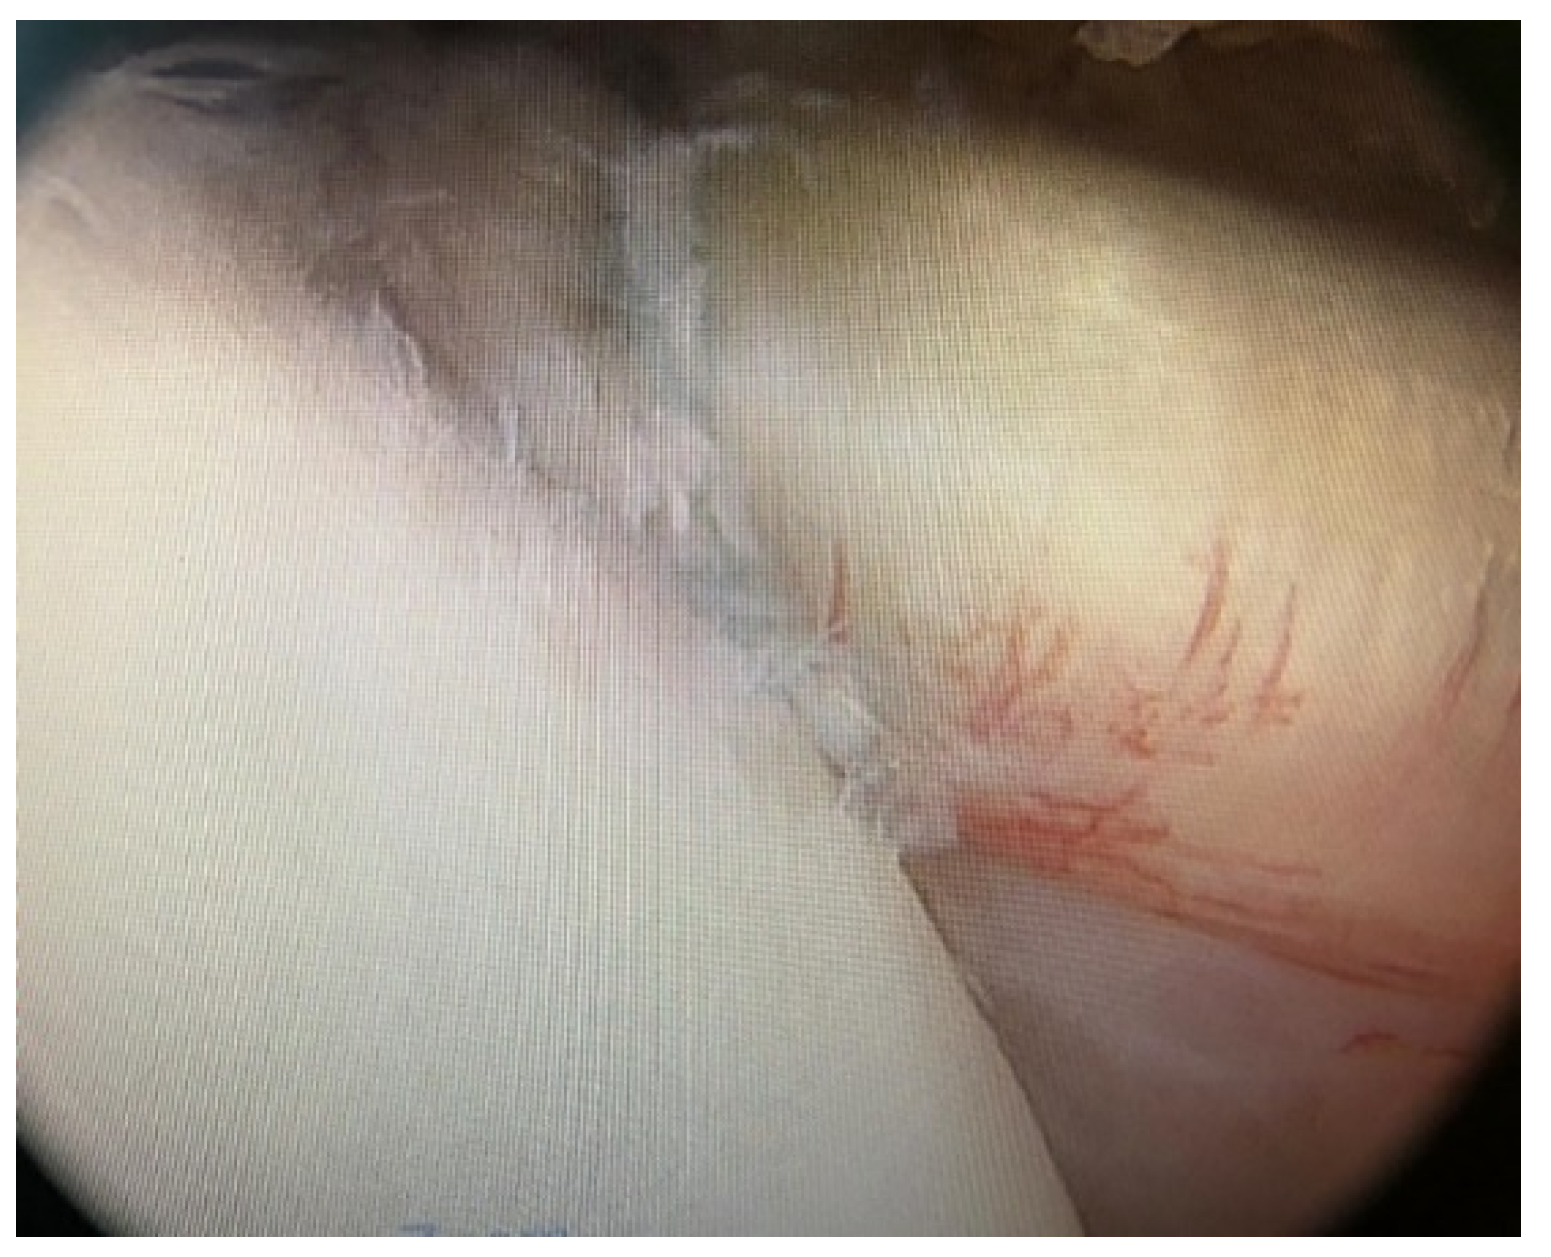

Posterior Shoulder Dislocation with Engaging Reverse Hill–Sachs Lesion: A Retrospective Study of Ten Patients Treated with Arthroscopy or Open Reduction and Stabilization

3. Results